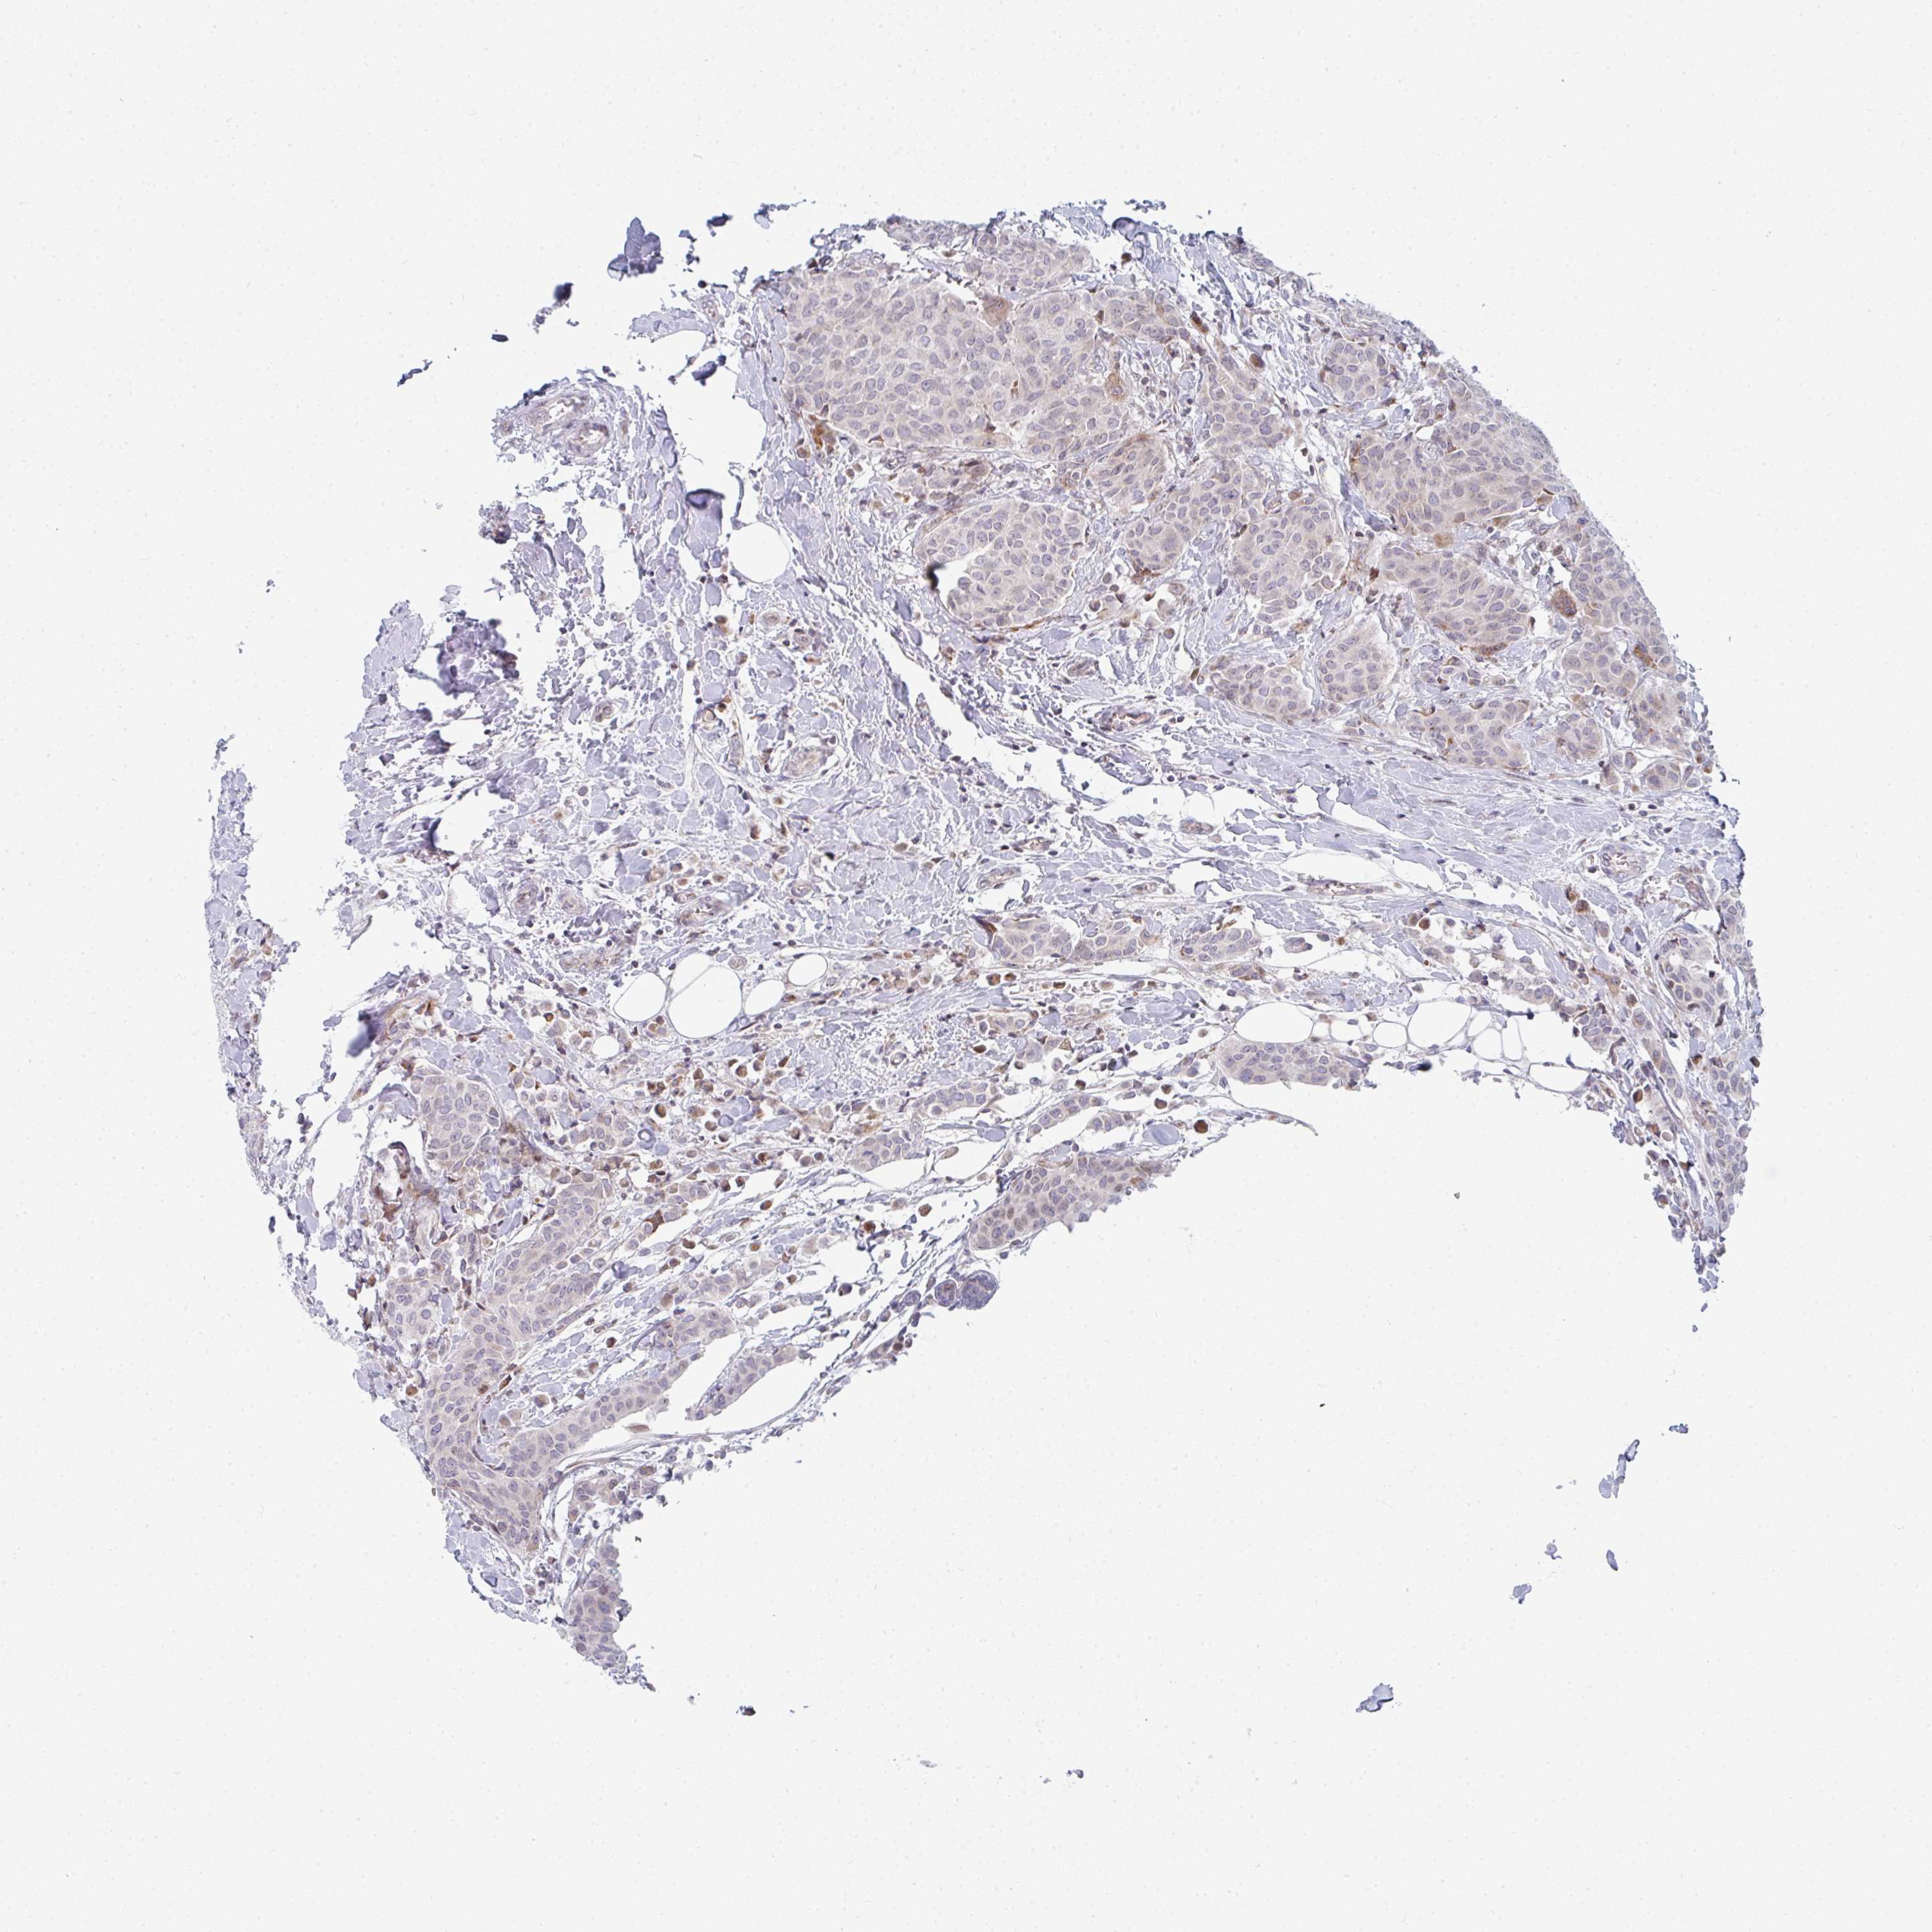

CANCER BREAST CANCER Show tissue menu

BRCA TCGA BRCA VALIDATION PROTEIN EXPRESSION

Breast cancer

Human cancer

Breast invasive carcinoma